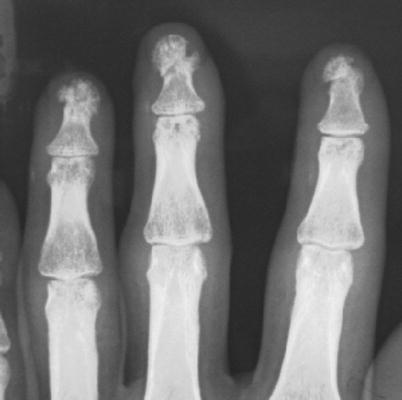

Fig. 8.20

(a, b) Procedure 10: Appearance of nails 1 year later. Healthy nail growth can be seen. The bulge on the palmar side of the fingertip has been accurately recreated. Return of sensory function is also recognized

Fig. 8.21

Procedure 11: X-ray image 1 year after surgery. No bone absorption in the finger tip. (Some photos reproduced from Hirase, Y., et al.: A new reattachment procedure for fingers amputated at the nail bed level. Journal of Japanese Society for Surgery of the Hand 20:501–504, 2003)